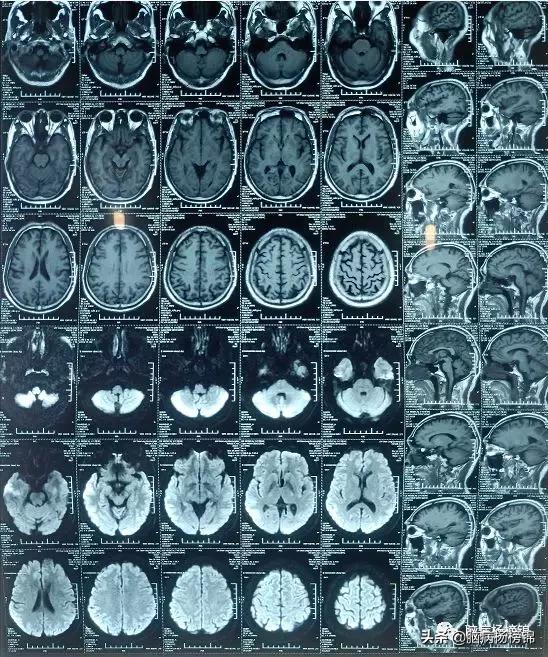

第二天上午,病人来到我院脑病科,错过溶栓时间段,建议做DWI

核磁共振平扫正常。

血管成像正常。